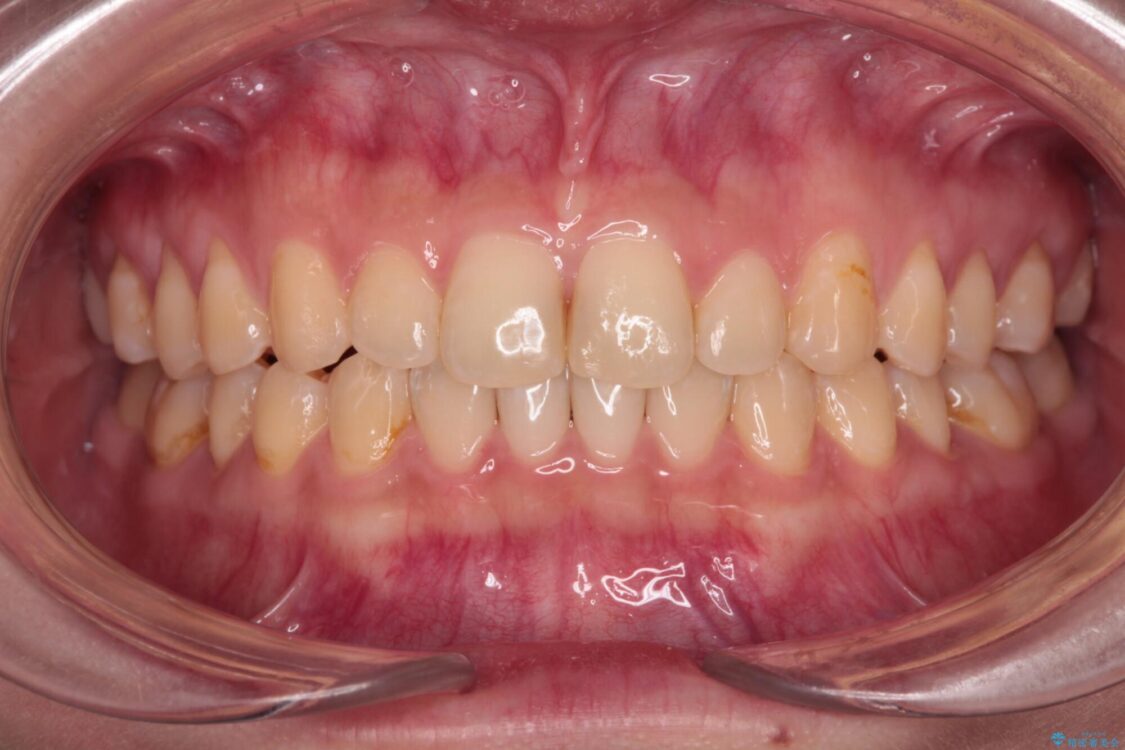

根管治療を行ったままの奥歯と、矯正治療の後戻りを気にして来院された患者様です。

矯正治療の後戻りは軽微であったため、インビザラインの簡易パッケージであるインビザライン・ライトを用いて歯列を整えることとしました。

治療前

• 治療途中の奥歯と矯正治療の後戻り インビザライン・ライトによる矯正治療 治療前画像